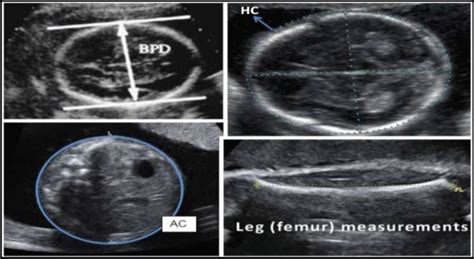

- BPD (Biparietal Diameter): This measures the diameter of your baby’s head from one side to the other. Think of it like measuring the widest part of their head. It’s one of the most common measurements and helps estimate how far along your pregnancy is and how well the head is developing.

- HC (Head Circumference): This measures the circumference, or the distance around, your baby’s head. It’s a key indicator of head size and brain development. Often, the HC measurement is used together with the BPD measurement for a more accurate assessment.

- AC (Abdominal Circumference): This measures the circumference of your baby’s abdomen. This measurement helps assess the baby’s weight and overall growth. It’s particularly useful in detecting potential issues like growth restriction or, on the other hand, the baby is too big for the gestational age.

- FL (Femur Length): This measures the length of your baby’s femur, which is the thigh bone. The FL can be used to estimate your baby’s gestational age and size, just like the other measurements. It’s an important measurement because it can provide clues about skeletal development.